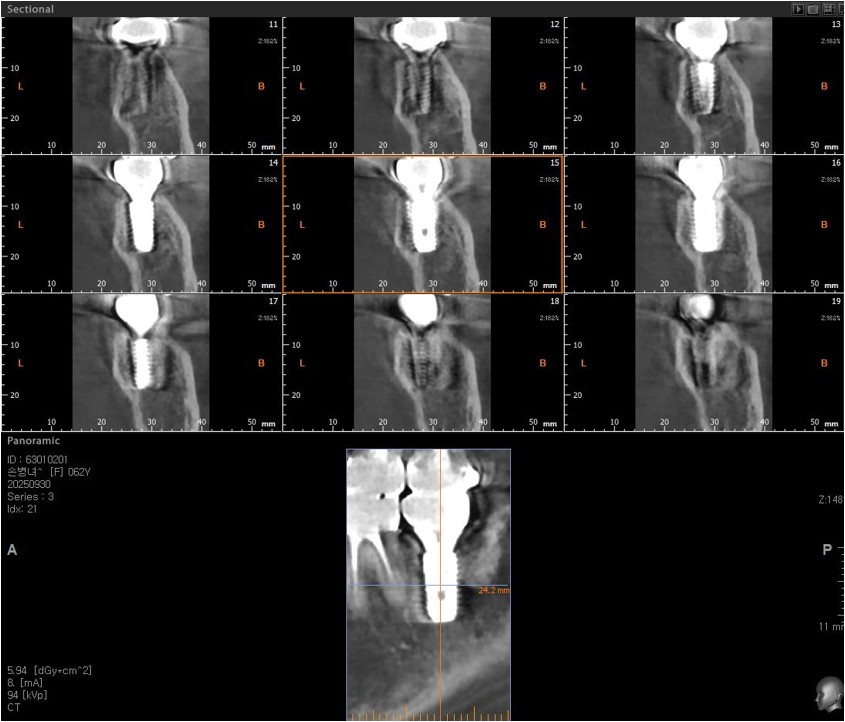

SIngle Implant - Immediate Placement, 8-year follow up

<CJ SBN> old female had mobility and pain when chewing in the lower molar